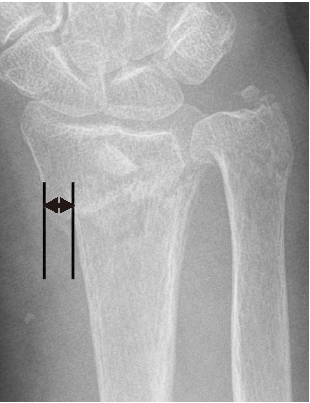

도수 정복 이후 측정한 원위 요골의 영상학적 인자들이 ‘허용 가능한 각도’의 범위일 경우에만 보존적 치료를 시작하였다. 요측 전위 정도는 손목의 전후방 X-ray 사진에서 원위 요골 골편의 요측 이동 정도를 의미한다(Fig. 1). 전후방 전위 정도는 손목의 측방 X-ray 사진에서 원위 요골 골편의 전후방 이동 정도를 의미한다(Fig. 2). 배측 피질골 파절 각도는 원위 요골 골편의 후방 피질골과 요골의 장축이 이루는 각도라고 정의하였다. 배측의 분쇄가 심한 경우에는 단순 방사선 영상에서 가장 뚜렷하게 관찰되는 후방 피질골을 기준으로 각도를 측정하였다(Fig. 3). 수배측 분쇄 골절은 측방 X-ray 사진에서 원위 요골의 수배측에 별개의 골절편(free-floating bony fragment)이 존재하는 경우로 정의하였다(Fig. 4).18) 모든 영상학적 인자들은 도수 정복 전의 초기 단순 방사선 사진 또는 컴퓨터 단층촬영 영상을 토대로 측정되었다. 본 연구는 본원 기관생명윤리위원회(Institutional Review Board, IRB)의 승인(IRB No. 2022-01-013)을 받아 시행한 연구로, IRB에 의해 환자 서면동의서 획득은 면제되었다.

Fig. 2

Anteroposterior translation is defined as the distance of the anteroposterior side movement of the distal fragment in the lateral X-ray of the wrist. The black lines are perpendicular lines that pass the most dorsal point of the volar cortex of the distal fragment and the most volar point of the volar cortex of the proximal fragment. A double-headed arrow indicates the anteroposterior translation.